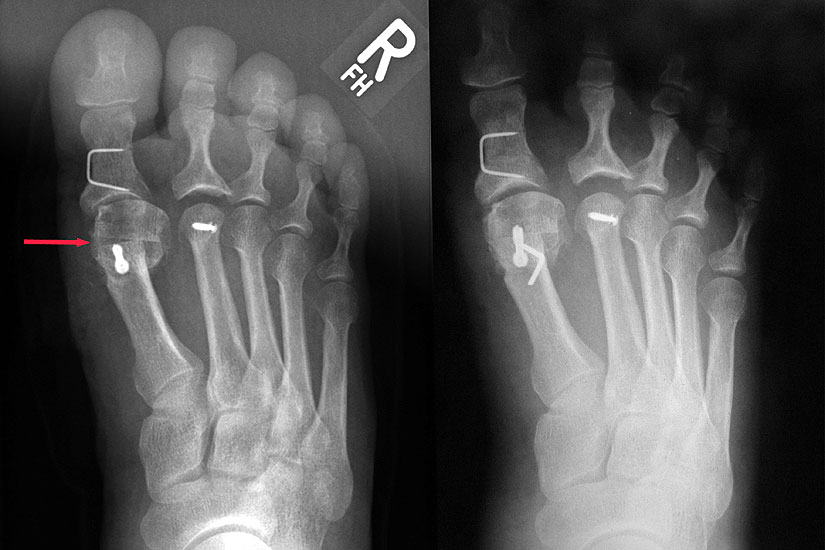

Abbildung 1

Klinische Untersuchung des gesamten Fußes unter Entlastung und Belastung

Röntgenaufnahmen des Fußes d.p., streng seitlich und schräg unter Belastung

Operationsplanung anhand der Röntgenaufnahmen unter Beachtung wichtiger radiologischer Landmarks wie Intermetatarsalwinkel, Hallux valgus – Winkel, Distaler Gelenkflächenwinkel (Distal metatarsal articular angulation: DMAA), Metatarsaleindex und Sesambeinposition (Abbildung 1)

Die Chevron Osteotomie ist eine der weltweit am häufigsten angewandten Verfahren zur Korrektur einer milden bis mittelgradigen Valgusfehlstellung der Großzehe 1110121319148. Die zahlreichen Publikationen berichten über relativ verlässlich gute und reproduzierbare Ergebnisse. Durch Modifikationen in der Operationstechnik versuchten einige Autoren den Indikationsbereich auf mittelgradige bis schwerwiegende Fehlstellungen auszuweiten 121314. Die Bestimmung des Schweregrades der Fehlstellung erfolgt in erster Linie am belasteten Röntgenbild im dorsoplantaren Stahlengang (siehe Abbildung 1). An dieser Aufnahme können die wichtigsten radiologischen Vermessungen zur Operationsplanung vollzogen werden 112310121312728172930, auch wenn in einigen Studien eine große inter- und intraindividuelle Schwankungsbreite der Messergebisse dargestellt werden konnte 2930. Ebenso zeigt sich eine gewisse Varianz in der Methodik zur Bestimmung des ersten Intermetatarsalwinkels 18282931. Als Grenzwerte für einen milden bis mittelgradigen Hallux valgus werden in der Literatur in relativ weiter Übereinstimmung ein Intermetatarsalwinkel bis maximal 16° und ein Hallux valgus Winkel bis 40° genannt 688. Der DMAA ist radiologisch schwierig zu beurteilen und sollte intraoperativ bei Gelenkeröffnung inspektorisch überprüft werden 2. 2007 verglichen Trnka et al. (2007) die Ergebnisse von vier verschiedenen Nachuntersuchungsgruppen, die sich durch Modifikationen der OP Technik unterschieden: 66 Chevron Operationen von 1991 bis 1992, 100 Chevron Operationen von 1992 bis 1995, 55 Chevron Operationen von 1994 bis 1995 und 89 Chevron Operationen von 2000 bis 2002. So wurde der dorsomediale Zugang 1992 durch einen streng medialen Zugang mit L-förmiger Kapsulotomie ersetzt. 1992 wurde das laterale Release über einen dorsalen Zugang eingeführt mit Perforation der lateralen Kapsel längs zwischen Metatarsale 1 und fibularem Sesambein, sowie vertikal im Verlauf der Gelenklinie ohne Ablösung des Adduktors oder Durchtrennung des intermetatarsalen Bandes. Zwischen 1994 und 2000 wurde eine temporäre Fixation mit einem Kirschnerdraht durchgeführt. Seit 2000 wird die Osteotomie mit einer kanülierten Kompressionsschraube fixiert. Insbesondere die Einführung des lateralen Release führte zu einer signifikanten Verbesserung des Hallux valgus- und Intermetatarsalwinkels, ohne vermehrt Probleme mit einer avaskulären Nekrose des MTK 1 zu bekommen. Die Einführung einer Osteosynthese mittels Kirschnerdraht zeigte im follow up nach 34 Monaten gegenüber der lediglich manuellen Einstauchung des distalen Fragments, wie in der Originalarbeit von Austin beschrieben, eine geringere Rate an Korrekturverlusten und Dislokationen des ersten Metatarsaleköpfchens. Durch die Verwendung einer Schraube konnte das Indikationsspektrum hinsichtlich Schweregrad des Hallux valgus erweitert werden. Der Vergleich einer 2-Jahres- und eines 5-Jahres-Nachuntersuchung zeigte gegenüber der präoperativen Untersuchung eine Verbesserung des IM-Winkels von 13° auf 8° respektive 9°. Der HV-Winkel konnte von durchschnittlich 29° auf 15° respektive 16° reduziert werden. Ergebnisse, welche auch die langfristige Zuverlässigkeit der Chevron-Osteotomie in der Behandlung des milden bis mittelgradigen Hallux valgus belegen.